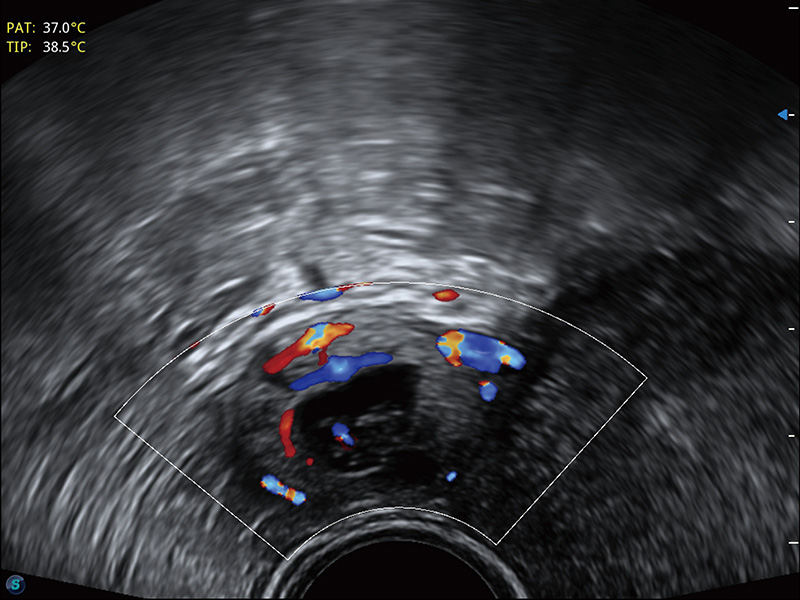

“生育问题”即关系民族复兴,也关系亿万家庭的幸福。随着婚育年龄推迟、社会压力增加等因素,越来越多人群也面临着“生不出、生不好”的问题。辅助生殖作为治疗不孕不育最有效的方法之一,也逐渐成为育儿新希望。而超声检查能为生殖需求人群的初诊评估提供宝贵的信息。 P20 Elite是玖鼎集团匠心打造的一款生殖应用型彩超。她继承玖鼎集团高端极光平台,突破性地将多款新型芯片及硬件模块进行整合,均衡了高端系统性能与小巧灵动机身。P20 Elite卓越的图像质量搭载专科探头,旨在为您提供全面的辅助生殖解决方案。

P20 Elite配备了丰富的生殖探头群和临床应用功能,在卵泡监测、穿刺取卵、胚胎移植、妊娠确认等领域,为生殖需求人群提供了新的临床机会,重新定义高端超声如何应用于生殖健康检查。